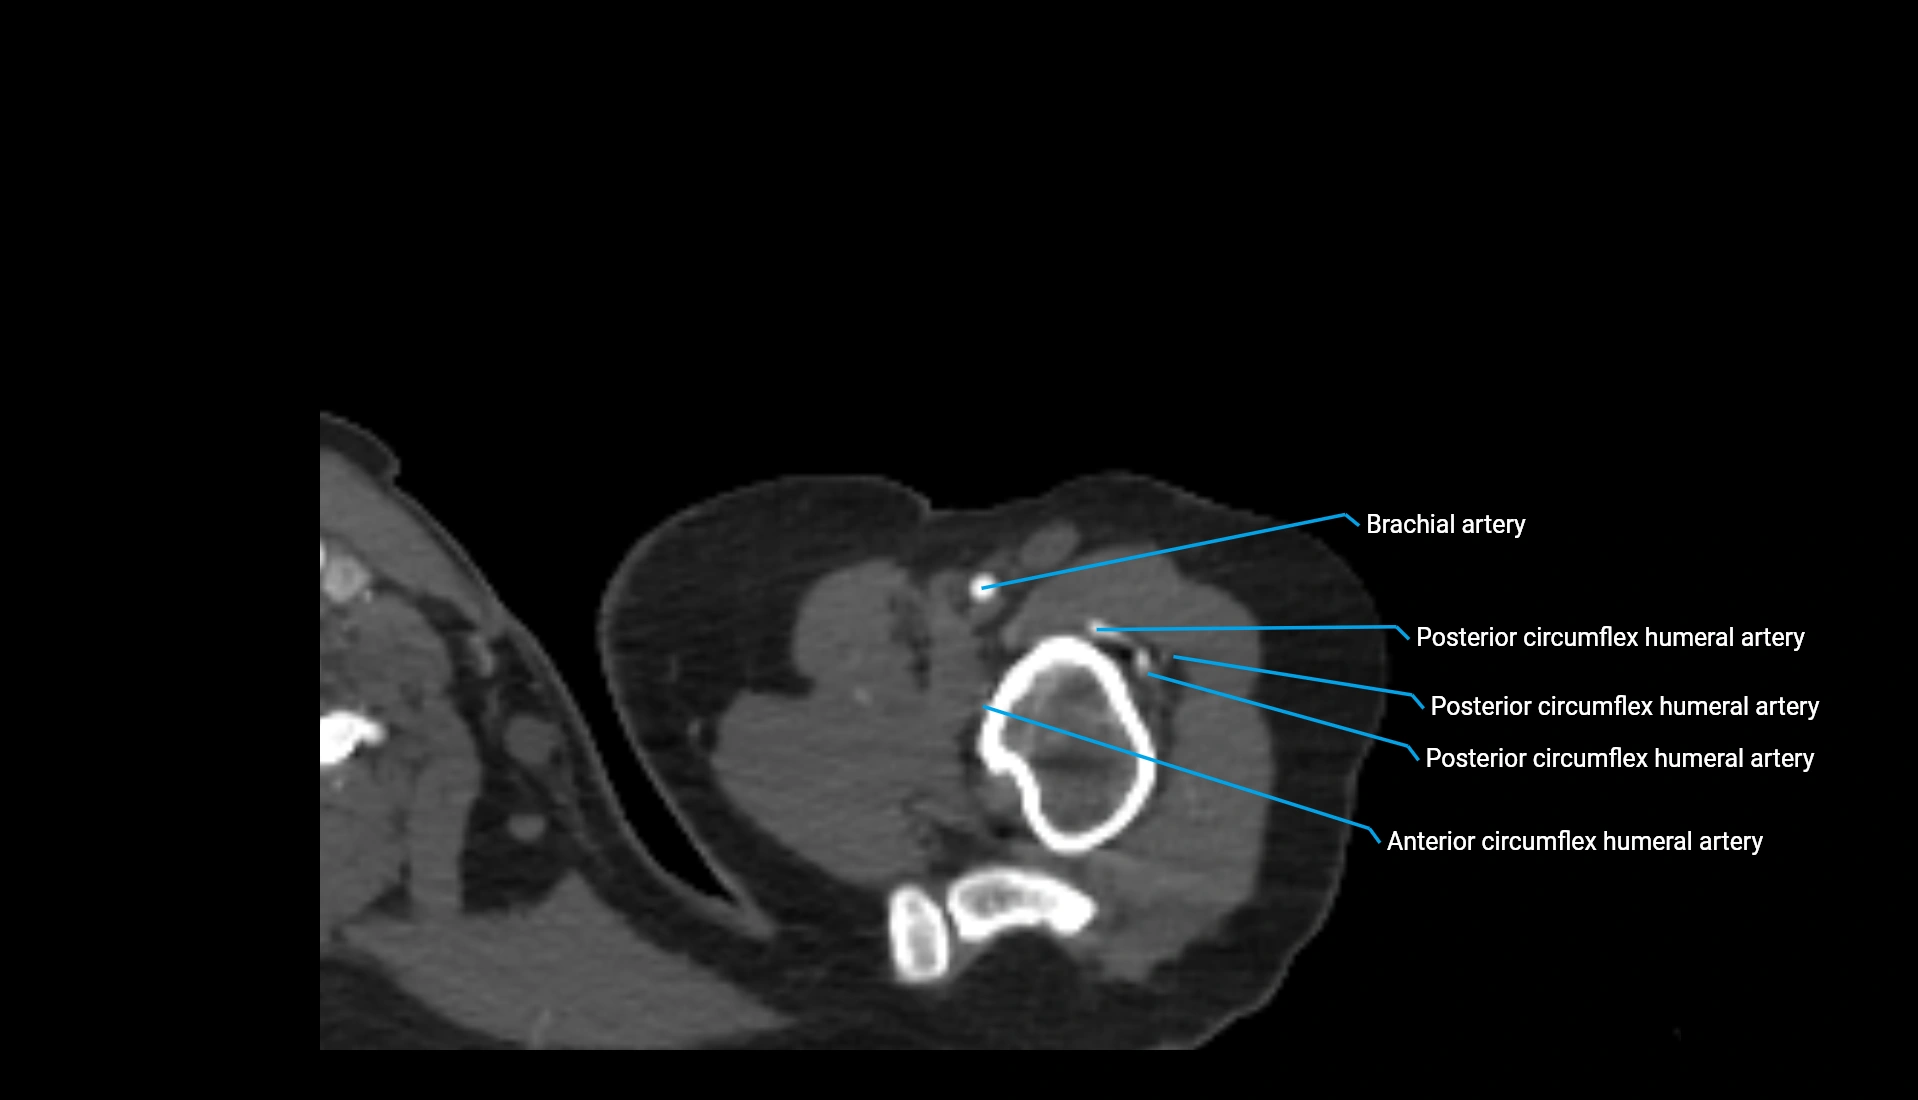

CT Appearance

Non-Contrast CT:

• Cortex: High-density, sharply defined

• Subchondral bone: Dense cancellous matrix

• Articular surface: Smooth concave contour articulating with the capitellum

• Excellent for evaluating bone integrity, alignment, and subtle fractures